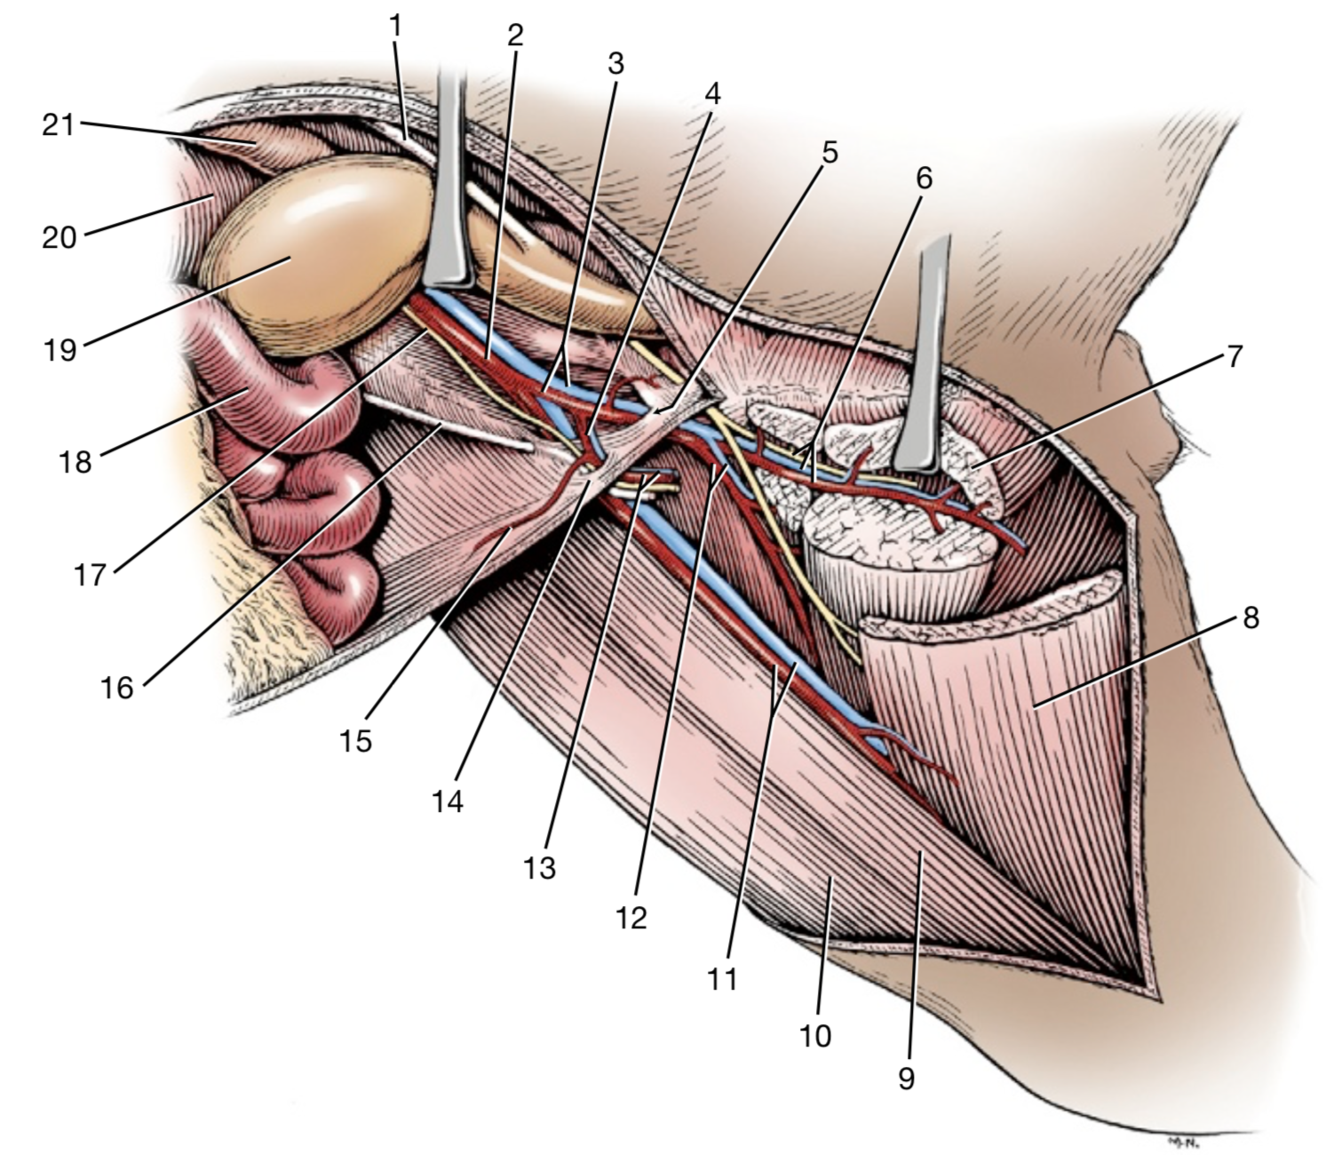

3

A./v. profunda femoris

- Ex a./v. iliaca externa

- Branches:

- Tr. pudendoepigastrica

- A. epigastrica caudalis

- A. circumflexa femoris medialis

Q

Tr. pudendoepigastrica

- Branches:

- A. pudenda externa

- A. epigastrica caudalis

Q

A./v. pudenda externa

- Through canalis inguinalis

- Branches: a. epigastrica caudalis superficialis

Q

A. epigastrica caudalis

- Supplies m. rectus abdominis

- Through canalis inguinalis

- Branches:

- **A. labialis/scrotalis ventralis